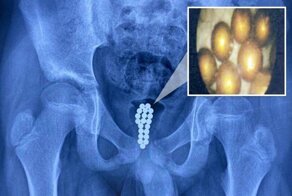

- В Китае врачи вытащили из пениса мальчика 20 магнитных шариков